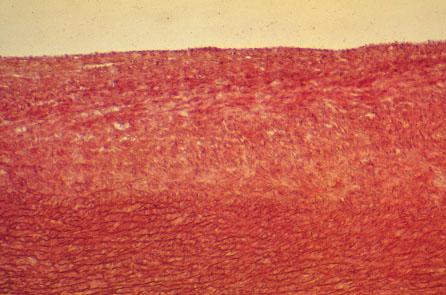

VI-25 (4) Slide 28, Aorta (H&E). Medium power view of aorta. Tunica intima is unusually thick (may be pathogenic?). Tunica media contains numerous elastic laminae synthesized by smooth muscle cells.